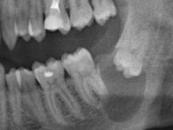

Седьмой передний зуб, выросший у хорька после воздействия препарата

Ключевой механизм препарата заключается в дезактивации белка USAG-1, подавляющего рост зубов. Позднее лекарство позволит не только способствовать их росту, но и восстанавливать зубы тем, кто потерял их из-за кариеса или травм.